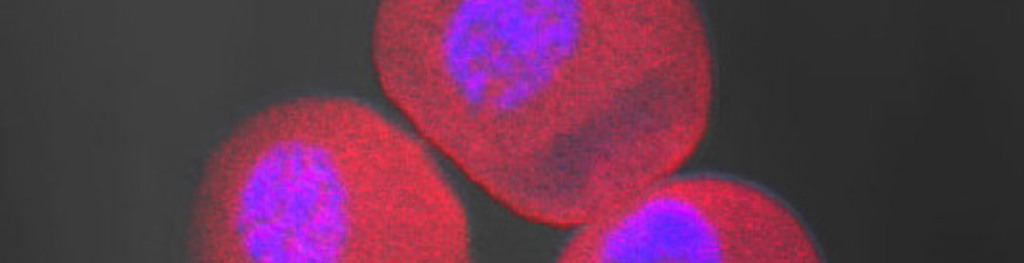

Our prostate cancer confirmation test kit, using a novel biomarker, can eliminate 1.3M prostate biopsies annually. Our simple urine test returns results in 24 hours, has 99% sensitivity and 100% specificity in the detection of prostate cancer.